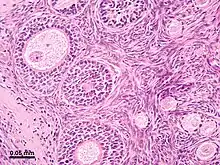

The surface of the ovaries is covered with a membrane consisting of a lining of simple cuboidal-to-columnar shaped mesothelium,[7] called the germinal epithelium.

The outer layer is the ovarian cortex, consisting of ovarian follicles and stroma in between them. Included in the follicles are the cumulus oophorus, membrana granulosa (and the granulosa cells inside it), corona radiata, zona pellucida, and primary oocyte. Theca of follicle, antrum and liquor folliculi are also contained in the follicle. Also in the cortex is the corpus luteum derived from the follicles. The innermost layer is the ovarian medulla.[8] It can be hard to distinguish between the cortex and medulla, but follicles are usually not found in the medulla.

Follicular cells are flat epithelial cells that originate from surface epithelium covering the ovary. They are surrounded by granulosa cells that have changed from flat to cuboidal and proliferated to produce a stratified epithelium.